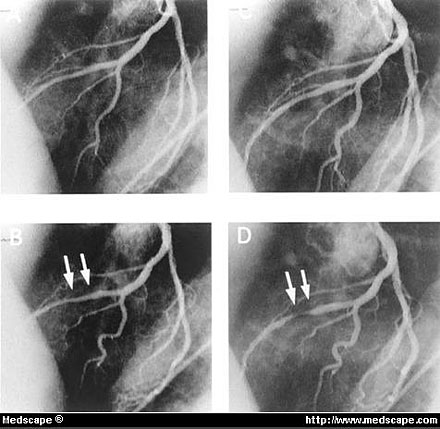

Representative case with CMB augmented by nitroglycerin.

A, Before nitroglycerin there were minor luminal irregularities in middle portion of LAD in diastole.

B, In systole, this segment was slightly narrowed by CMB.

C, After nitroglycerin, coronary segments including CMB dilated in diastole.

D, Under these conditions, CMB was markedly augmented as observed by angiography in systole.